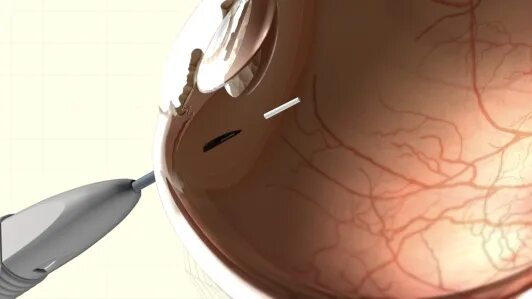

Озурдекс имплантат для интравитреального